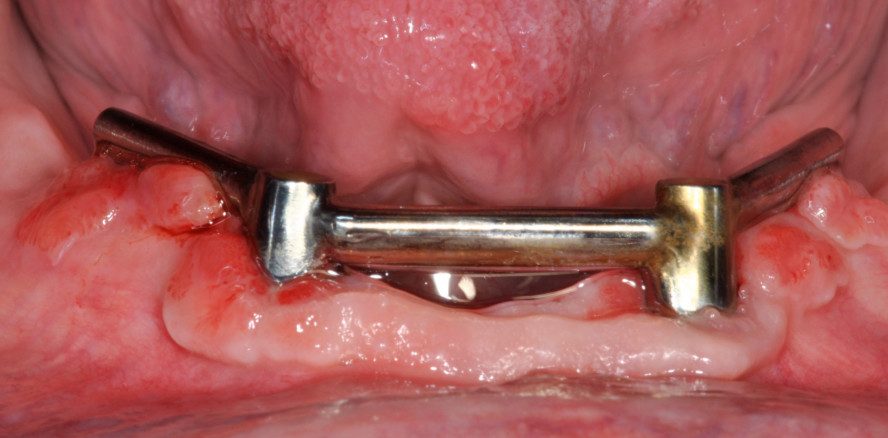

Weitere biologische Komplikationen sind Gingivahyperplasien, besonders unter Stegen (Abb. 7). Die genaue Pathogenese ist unklar, man scheint aber hier mit einem einfachen, den mundhygienischen Hilfsmitteln zugänglichen Design, genügend interimplantärem Abstand und natürlich guter Mundhygiene vorbeugen zu können. Bei wiederholtem Auftreten kann man sich überlegen, den Steg mit unverblockten einzelnen Attachments zu ersetzen, um so die Hygiene zu erleichtern.

Stege bieten eine sehr gute Retention und Stabilität, werden deshalb von Patienten sehr geschätzt und benötigen im Vergleich zu anderen Attachments wenig Nachsorge. Goldstege wurden unterdessen von CAD/CAM-gefertigten, individualisiert gefrästen Titanstegen abgelöst (Abb. 11). Nicht nur aus Kostengründen, sondern auch die Materialverarbeitung durch Fräsen aus einem soliden Block, bietet enorme mechanische Vorteile.

Wie die Nachuntersuchung von Katsoulis et al. 2011 zeigt, weisen sie im Vergleich zur Gruppe mit Goldstegen keine Frakturen und deutlich weniger Nachsorgearbeiten auf. Interessanterweise scheinen Titanstege auch deutlich weniger Gingivahyperplasien zu verursachen, was weiter für sie spricht. Es muss jedoch berücksichtigt werden, dass nicht alle Patienten gut mit einer Stegarbeit zurechtkommen. Besonders solche mit manueller Beeinträchtigung können Mühe haben, den Steg sauber zu halten oder die prothetische Arbeit selber aus dem Mund zu entfernen. Auch sind die Herstellungskosten im Vergleich zu vorfabrizierten Attachments höher und wenn Nachsorgebedarf besteht, muss oft mit dem zahntechnischen Labor zusammengearbeitet werden.